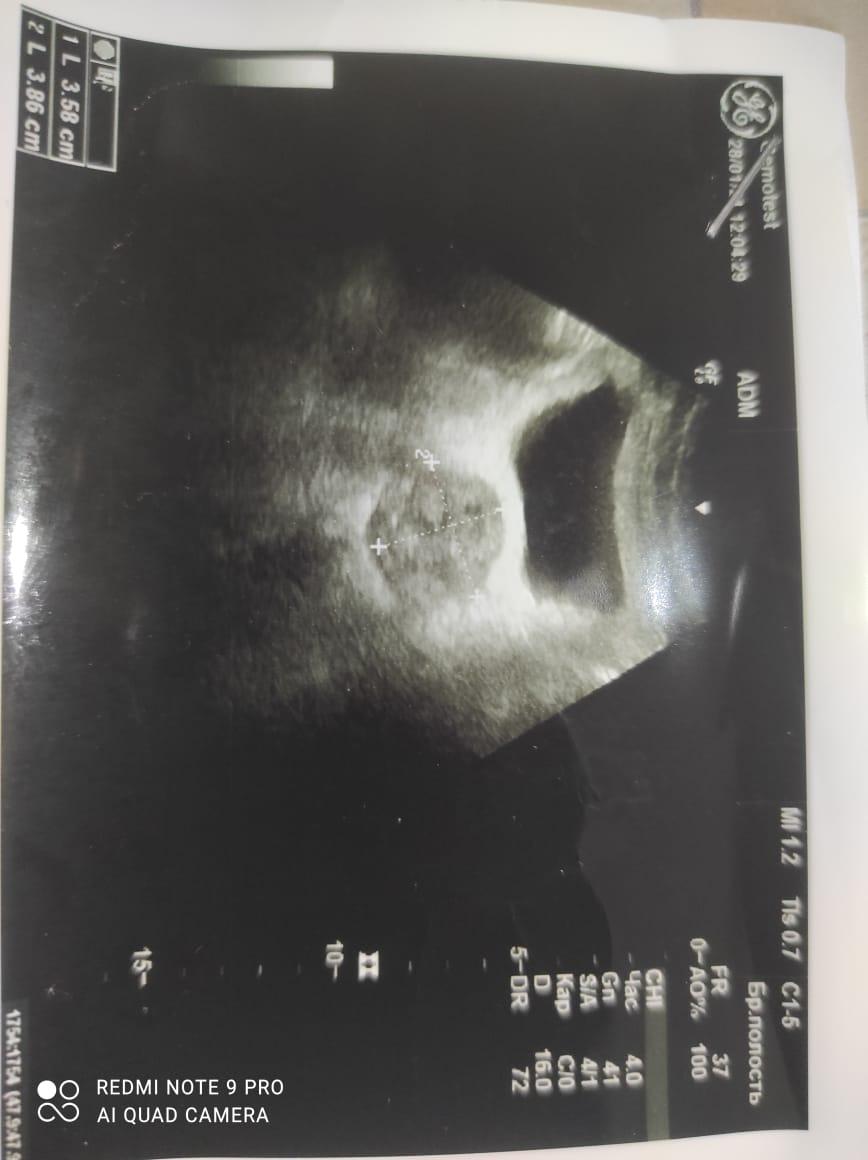

Здравствуйте! При наличии коралловидного камня правой почки(заключение УЗИ), можно предположить причиной боли нарушение уродинамики верхних мочевых путей), что, однако, не подтверждается результатами УЗИ почек( ЧЛС не расширена). Другая, наиболее вероятная возможная причина "боли в боку" - может быть патология опорнодвигательного аппарата. Необходимо проконсультироваться с неврологом и урологом очно, и согласовать возможность применения противовоспалительных, обезболивающих и спазмолитических препаратов - как первый шаг. В дальнейшем необходимо планировать возможное дальнейшее обследование и лечение. Удачи!